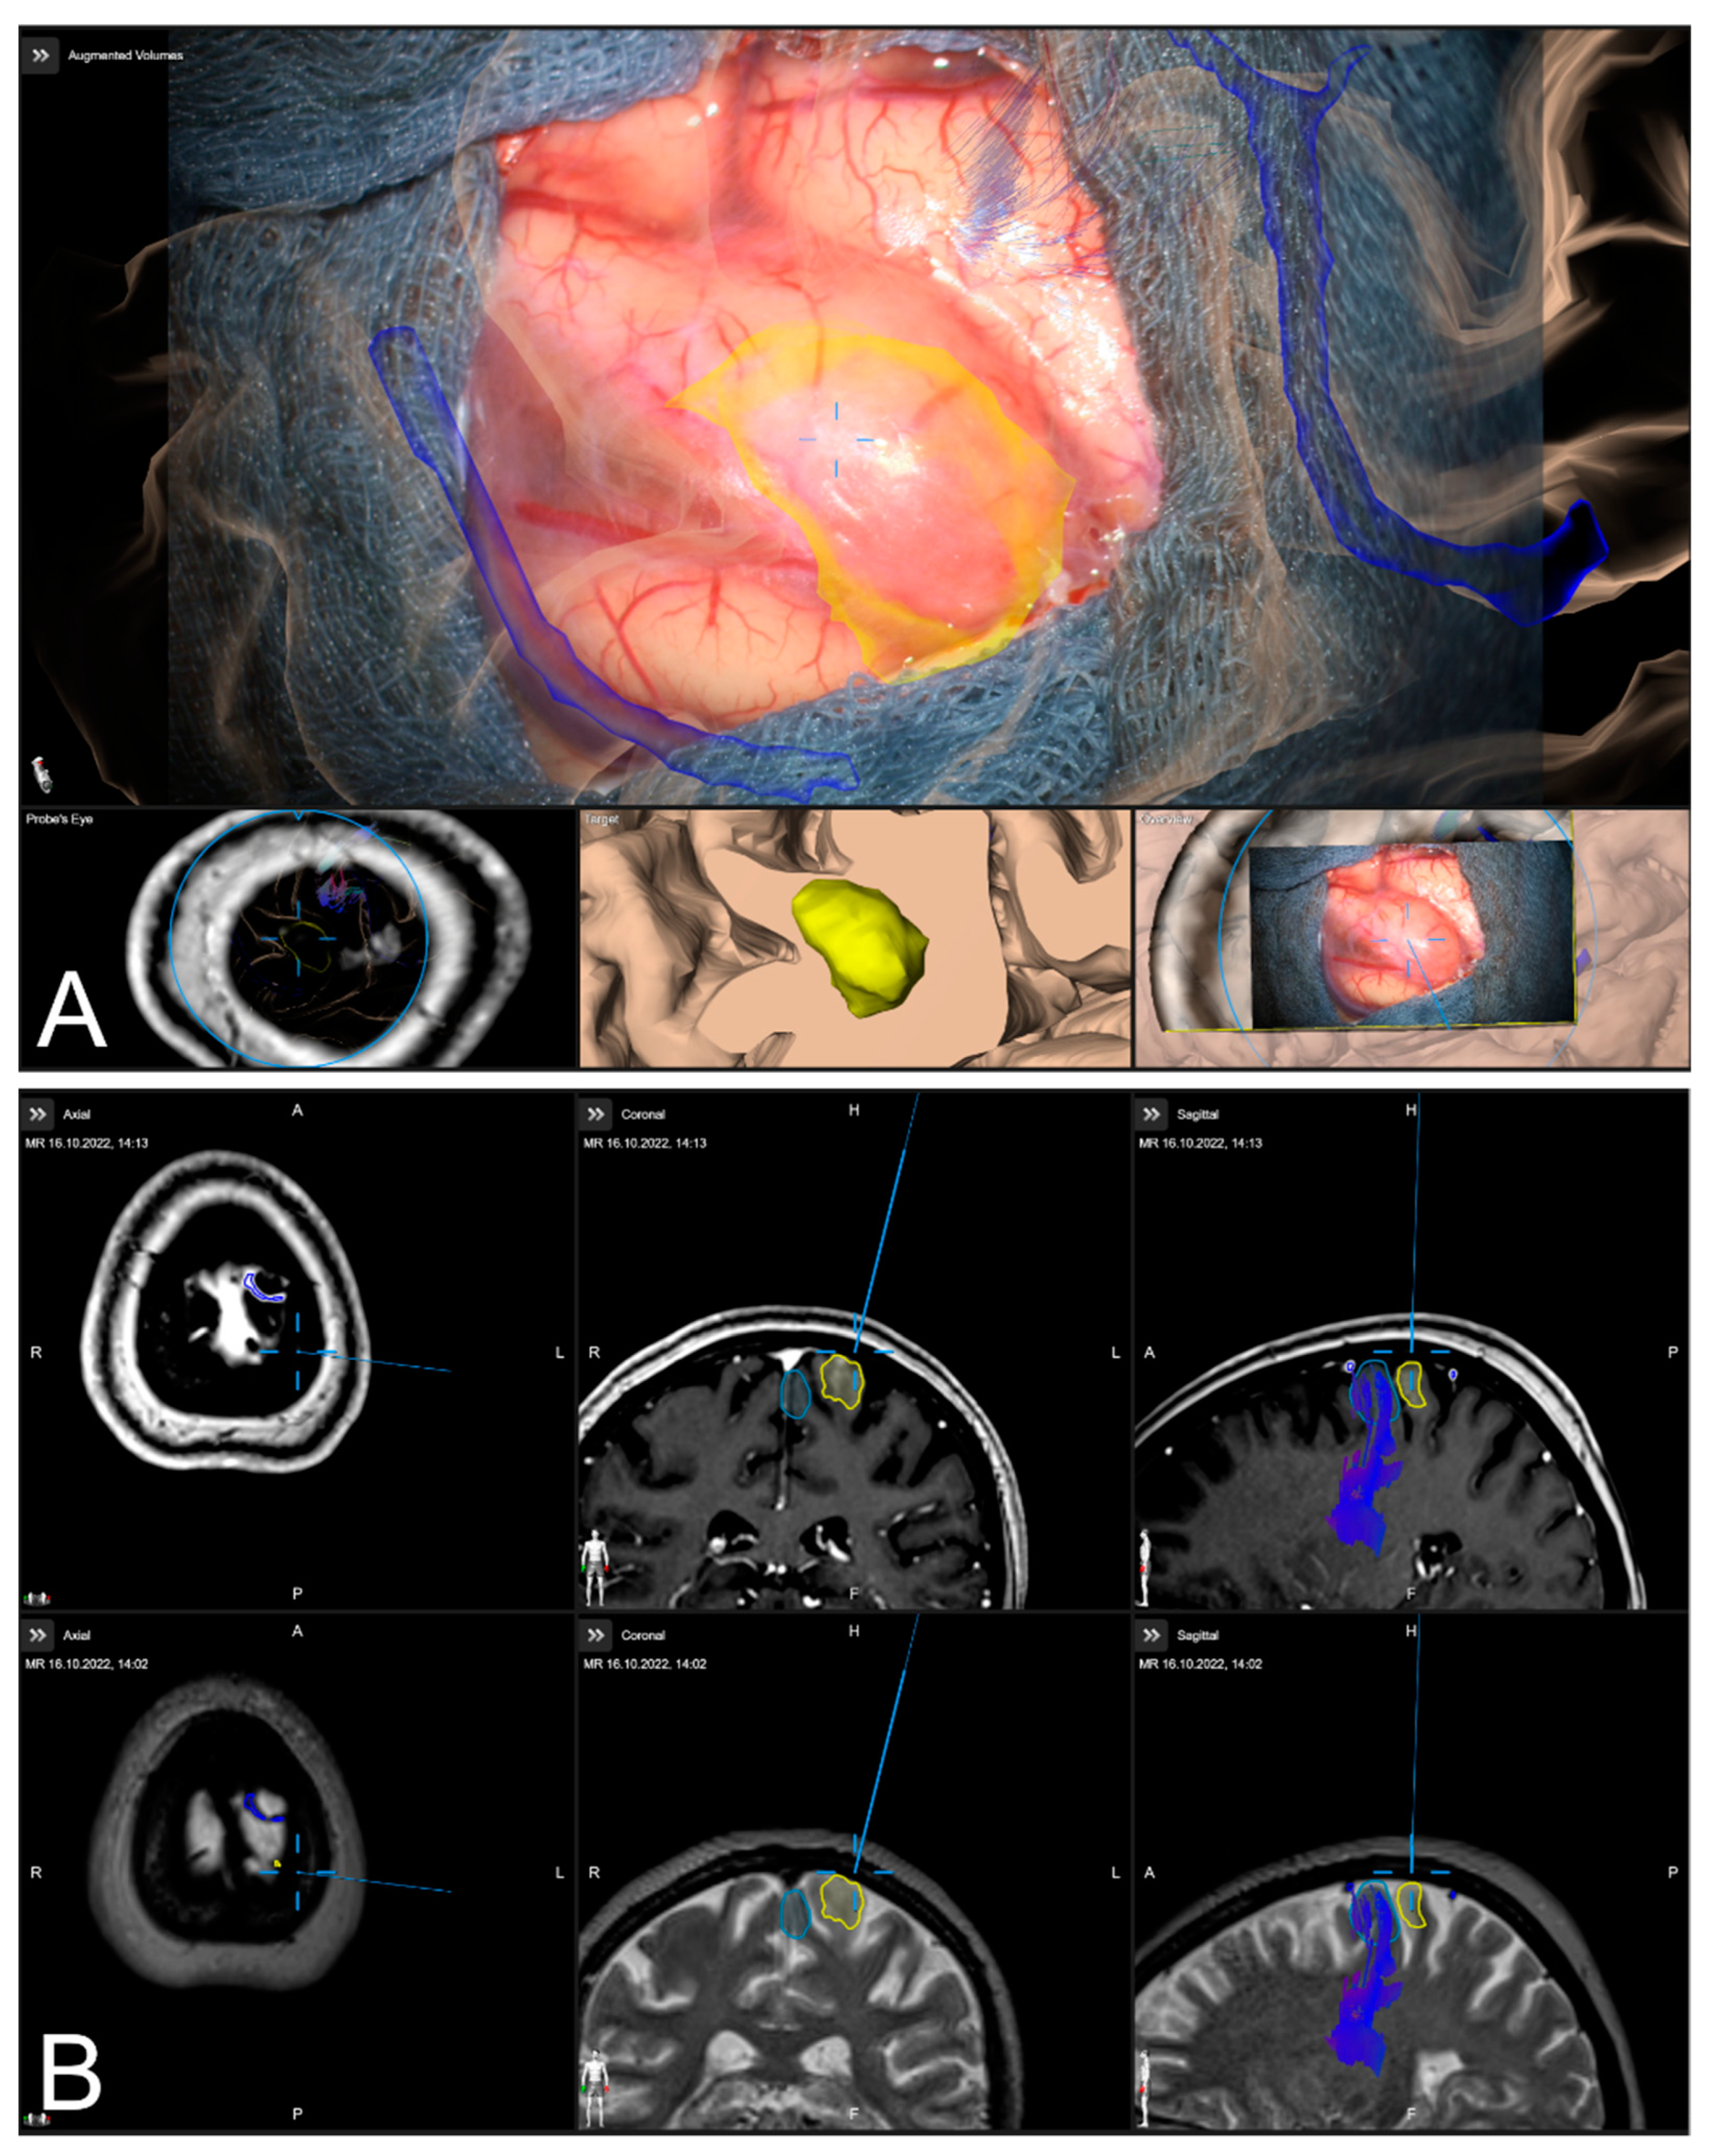

Figure 8. High spatial navigation accuracy seen in the recent focus plane utilizing a MIP of a preoperative T1-CE image (A,C), and patient anatomy enhanced with segmented vascular structures (blue), tumor outlines (yellow) and precentral gyrus (green) (B,D) in two patient cases, showing the different quality of preoperative imaging data (In parallel view of MIP projection and patient anatomy (upper part) and inline views with the recent focus plane (blue line) and the optical axis (dashed blue line) in the bottom part).

Sensors 22 09591 g008

In 242 cases (82.59%), a vascular representation gained by available preoperative CTA, T1-CE, or ToF angiography data was used to evaluate navigation accuracy after dural incision, whereas in the remaining 18 cases (6.14%), no sufficient representation of cortical vascular structures could be obtained due to a lack of sufficient 3D data or poor contrast enhancement. In 43 out of those 242 cases (17.77%), a need to further realign the image data within the recent focus plane (see Figure 7) was seen, whereas in 181 cases (74.79%), navigation accuracy was determined to be sufficient (see Figure 8), partially due to prior evaluation utilizing bony landmarks. In all 43 cases, showing an inaccurate match of image and patient data, these local inaccuracies were successfully compensated for by rigid 2D transformation of the image data by translation on average of 3.00 ± 1.93 mm and a rotation on average of 0.38° ± 1.06°.

2.4.2. Verification of Navigation Accuracy Using Cortical Vessels

Navigation accuracy can also be evaluated using cortical vessels. After durotomy, the apparent cortical vessel structures can be used to investigate the accuracy, either verifying accuracy or trying to compensate for inaccuracies. A MIP representation is thereby created by image data ideally clearly picturing vessels, such as CT angiography data (CTA), T1 contrast-enhanced MRI data (T1-CE), or MR time-of-flight angiography data (ToF). Focusing on prominent cortical vessels, especially close to branching, within the surgical site the corresponding MIP representation of vessel structures is visualized, and navigational accuracy can be evaluated. If a mismatch is seen within the recent focus plane, those inaccuracies can be compensated again by a rigid transformation of the image data. In case a proper vessel segmentation is available besides the MIP representation also the object representation can be used. Especially in cases where no proper data for a MIP-based vessel representation is available a manual segmentation of cortical vascular structures within, e.g., T2 weighted MRI data can be utilized. If corrected, the new registration that is applied for further navigation needs to be verified as described above.